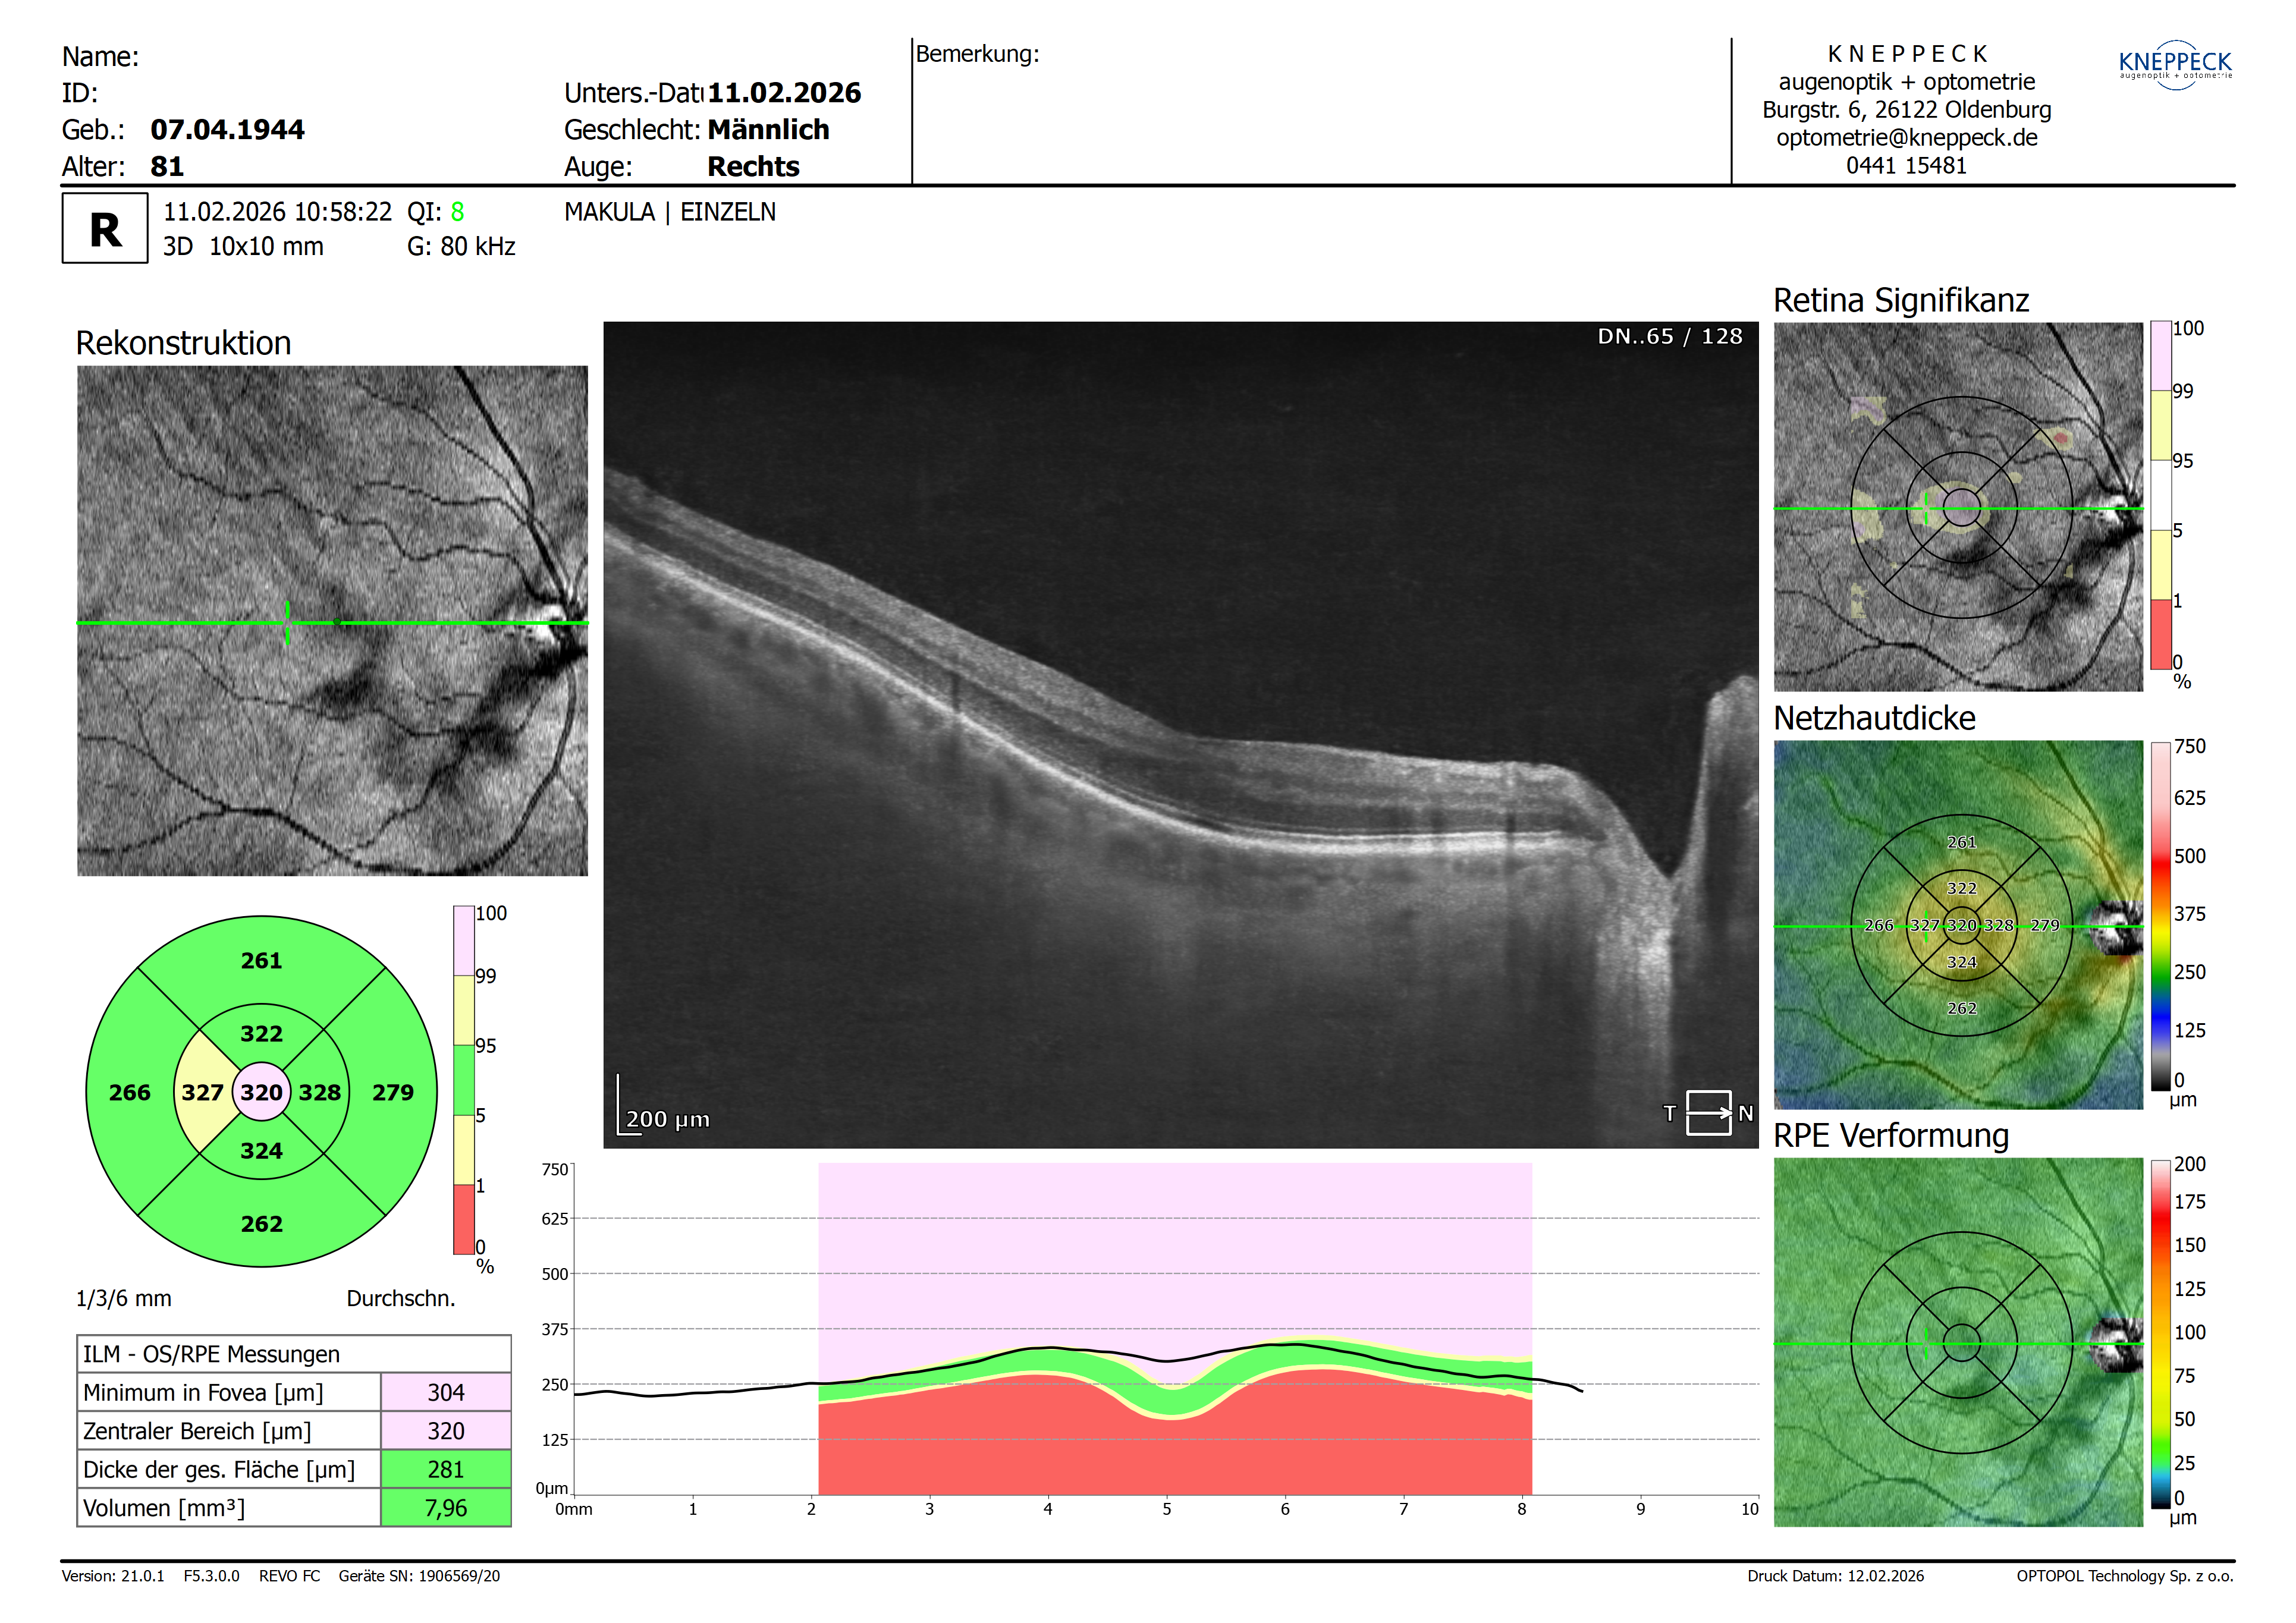

bei meinem Neukunden ist die foveale Senke bei beiden Augen kaum noch vorhanden. Eine Gliose besteht nicht.

ja, tatsächlich erkennt man hier eine abweichende zentrale Formation. In der OCT – insbesondere in der grafischen Darstellung unterhalb des B-Scans – wirkt die foveale Senke beidseits deutlich abgeflacht. Der erste Gedanke geht dabei natürlich in Richtung einer Gliose, was sich auf den ersten Blick jedoch nicht eindeutig bestätigen lässt. Gleichzeitig wissen wir, dass die Foveakonfiguration interindividuell eine gewisse Variabilität aufweist und nicht jede Abweichung zwingend einen pathologischen Korrelat haben muss.

Ich denke allerdings, dass sich das Phänomen hier recht plausibel erklären lässt: Der vorhandene Nachstar führt zu einer reduzierten Lichttransmission und damit zu einem abgeschwächten Reflektivitätsmuster in der OCT. Dadurch wirken die retinalen Schichten weniger kontrastreich, was die Beurteilbarkeit der fovealen Morphologie deutlich erschwert.

Bei genauerem Hinsehen zeigt sich jedoch auf fovealer Ebene beidseits eine feine epiretinale Linie, sodass durchaus von einer zarten epiretinalen Gliose auszugehen ist, die die Fovea leicht deformiert. Diese wird durch die verminderte Signalqualität gewissermaßen „maskiert“ und ist daher nicht unmittelbar offensichtlich.

Zur Bestätigung dieser Einschätzung und gleichzeitig zur funktionellen Verbesserung erscheint eine Nd:YAG-Laserkapsulotomie des Nachstars sinnvoll. Dadurch wäre nicht nur eine Visussteigerung zu erwarten, sondern auch eine deutlich bessere OCT-Signalqualität. In der anschließenden Verlaufskontrolle sollte sich dann zeigen, ob die vermutete diskrete Gliose tatsächlich vorliegt und in welchem Ausmaß sie die foveale Kontur beeinflusst.